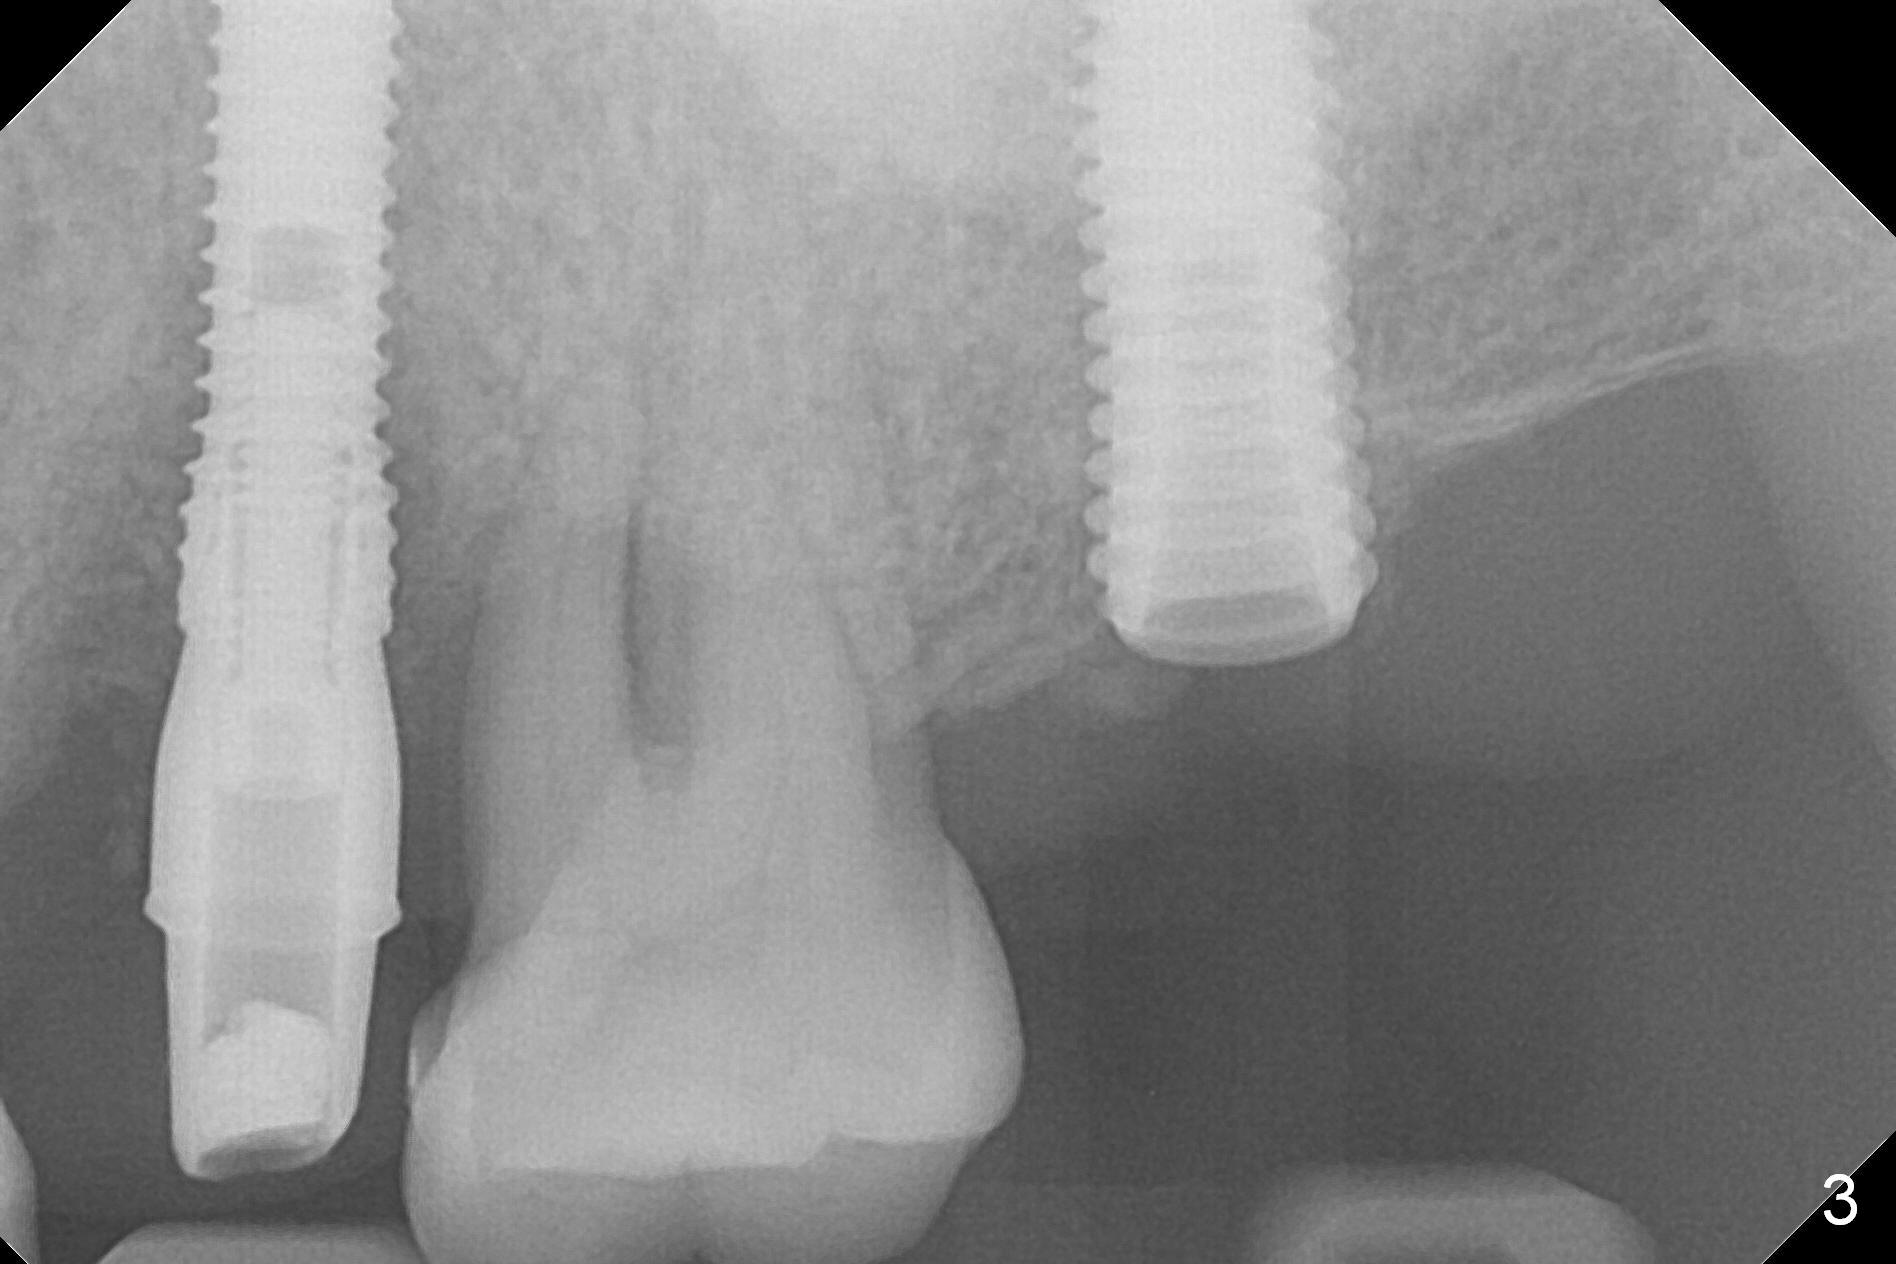

A 1.2 mm initial drill is used to start osteotomy at the site of #15 (Fig.1). After moving the osteotomy distally (with Lindamann bur), the osteotomy is enlarged by DIO Bone Expanders until 2.4/3.7 mm for 18 mm (gingival level) (Fig.2). Following the expander 3.0/4.4 mm, a 5x13 mm UF implant is placed supracrestal (Fig.3,4). After deepening the osteotomy with 3.8 mm drill for 3 mm, the implant is placed deeper by ~ 2 mm (Fig.5 arrow). Since the tooth #18 is supraerupted, a healing abutment (5.5x12(3) mm) is placed (Fig.6: H); the gingiva adapts to the abutment well. Suture is not necessary. The bone remains stable 2 and 4.5 months postop (Fig.7,8). Impression is taken. A crown is delivered nearly 6 months postop (08/07/2017). While there is minimal bone loss at #13 and 15 three years and 4 months post cementation, the tooth #14 and 18 are mobile (Fig.13,14, #13).